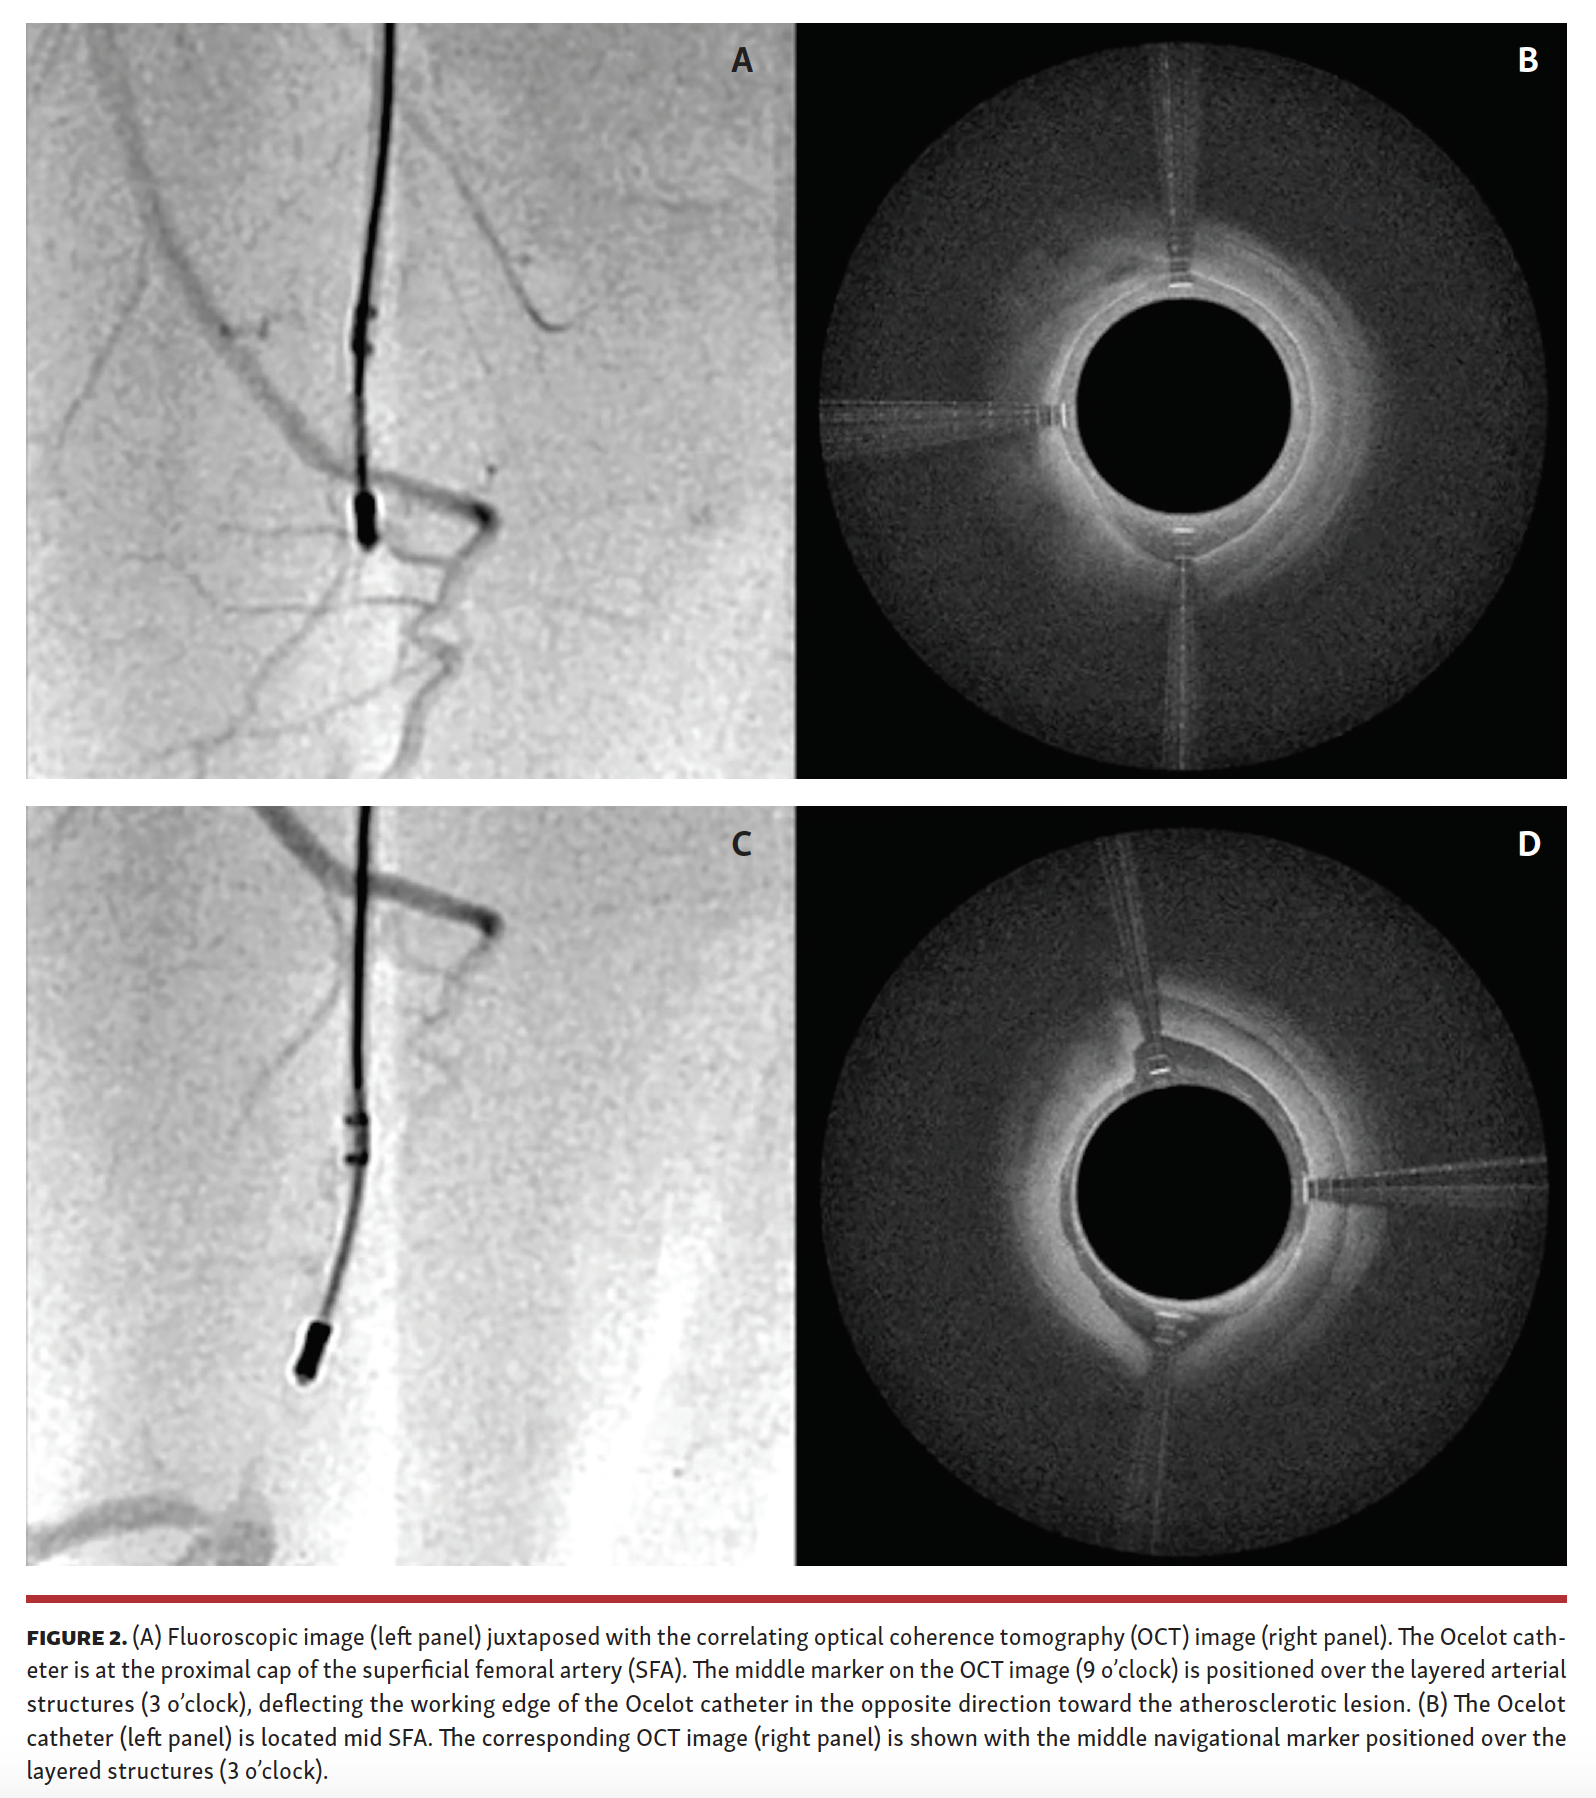

The patients were prepared for surgery following standard procedures. The target lesion was identified by angiography and its length was documented. With the lesion identified, the occlusion was traversed with an Ocelot crossing catheter (Avinger) (Figure 2) and then subsequently treated with TurboHawk directional atherectomy (Medtronic). Excised tissue was captured in the nosecone of the atherectomy device and collected at the end of the procedure, fixed in 10% neutral buffered formalin following standard methodology, and sent to the pathology lab.

A total of 19 patients participated in this pilot phase of the HIPACT study; they were predominantly male (67%) with a mean age of 72 ± 11.6 years. The CTO lesions were primarily (67%) in the superficial femoral artery (SFA), with 4 in a popliteal artery, and 1 each in the tibial peroneal trunk and the common iliac artery. All obstructions were crossed successfully by the crossing catheter with no dissections or perforations. Directional atherectomy reduced the obstructions such that blood flow was restored through the area of the obstruction, as determined by angiography. The amount of fluoroscopy time varied with the device used, with less than a minute of time (14 seconds) needed when the OCT-guided catheter was advanced through the obstruction to prepare a path for the atherectomy device (Figure 3).

In this study, the catheter used to cross the CTO has the capability of providing intravascular imaging via OCT on its cannula. This resulted in successful crossing in 100% of CTOs, and it was possible to maintain the cannula of the device within the center of the lumen of the vessel by monitoring the advancement of the catheter with its OCT imaging. Trauma to the vessel wall during CTO crossing has been associated with inflammatory cascades and can serve as a nidus for restenosis. In addition, the atherectomy device used in this study is guided by and monitored with angiography, which makes it a challenge to determine how deeply one is cutting into the layered structures of a peripheral artery during atherectomy. Use of an OCT-guided atherectomy catheter has been noted to result in low TLR rates at 6 months.